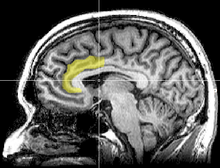

A study from the University of Sussex (UK) compared the brain structure of participants with the amount of time they spent on media devices i.e. texting or watching TV. [1]

The MRI scans of the participants, showed that the high multitaskers had less brain density in the anterior cingulate cortex. This is the brain region responsible for empathy and emotional control.

The implication of their findings, is that multitasking, especially involving the use of media devices, could permanently alter brain structure after a long period of usage.